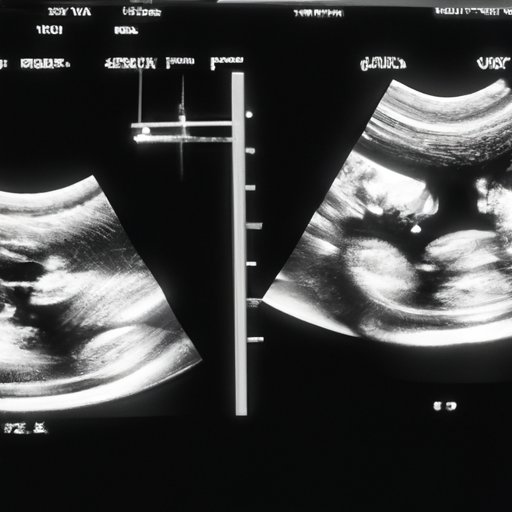

Ultrasounds are an essential part of prenatal care that...

Learn about the potential risks and expert opinions surrounding...